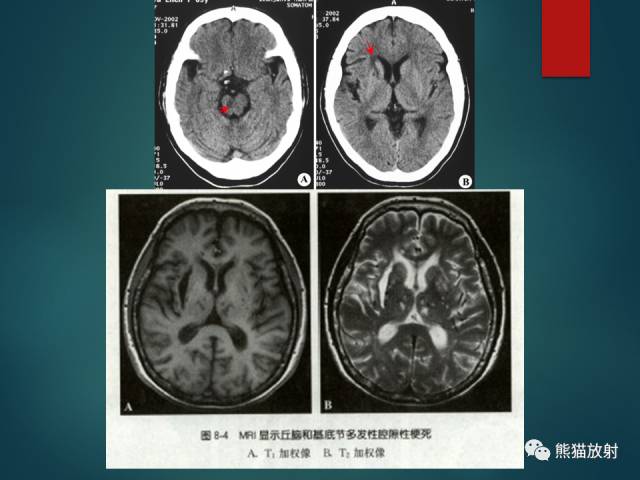

- 腔隙性脑梗死(LACI):颅内小动脉及穿支动脉狭窄或痉挛;T2-FLAIR呈高信号;DWI急性期弥散受限;基底节、脑干及丘脑多见。